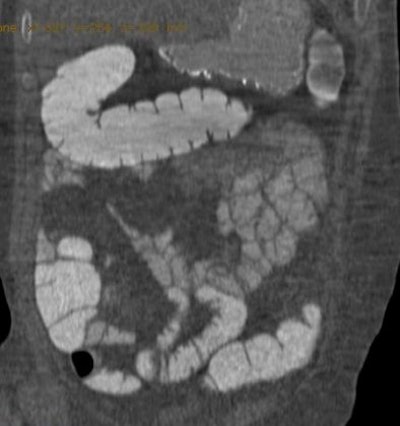

![]() |

| CT colonography from group A (same-day preparation). The coronal image shows good and homogeneous fecal tagging from the proximal to the distal colon. Image courtesy of Dr. Delia Campanella. |